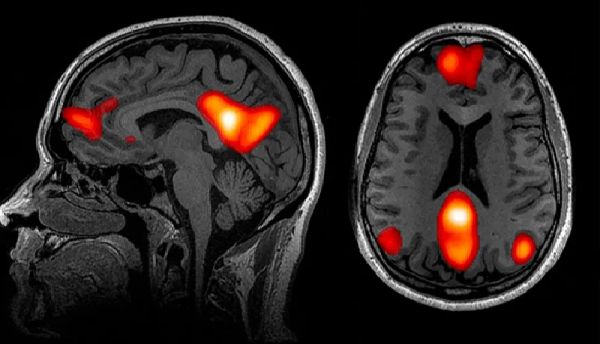

该研究2020年刊登于《自然-通讯》[21],其结果揭示了孤独感与当我们精神上处于待命状态时保持活跃的大脑默认网络(default network)密切相关。尽管研究表明默认网络中的活动消耗了大脑的大部分能量,“直到20年前我们都还不知道这一网络系统的存在。”比兹多克说。

比兹多克和他的团队发现长期孤独者的默认网络中某些区域的灰质体积不仅更大,而且他们的默认网络与大脑其他区域的连接也更紧密。此外,默认网络似乎参与了人类演化出的例如语言、预测未来和因果推理等独特能力的运用。更笼统地说,当我们想到他人时[22],包括当我们分析他们的意图时就会激活默认网络。

人脑的功能磁共振成像揭示了与默认网络相关的一些区域——当我们想到他人时最活跃的神经中枢区域。图片来源:John Graner,Terrence Oakes,Louis French and Gerard Riedy

心理学家早就发现,孤独的人往往会做社会互动的白日梦,容易怀念过去的社交事件,甚至拟人化他们的宠物[23],例如,与猫交谈。有关默认网络连接的研究,为该心理学发现提供了神经成像方面的证据,比兹多克说:“想要在心理上完成幻想需要默认网络做出相应的配合。”